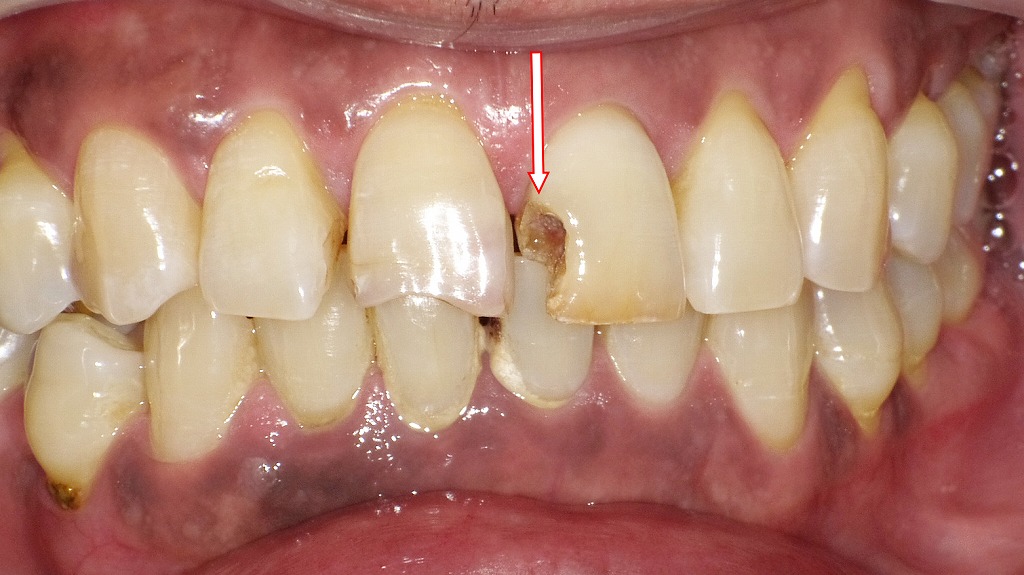

🎯 黒ずみ・柔らかさがある=虫歯の可能性

虫歯が原因で欠けた場合、欠けた部分の色や触感に特徴があります。

✅ 見分けポイント

- 欠けた部位が黒っぽい・茶色っぽい

- 舌や爪で触るとザラザラ、もろい、柔らかい

- 欠けた周辺の歯に冷たいものがしみる

🔍 特に要注意なのは「見えない奥歯の欠け」

奥歯の溝や詰め物の周囲は、虫歯が広がりやすく、欠けて初めて異変に気づくケースが多いです。